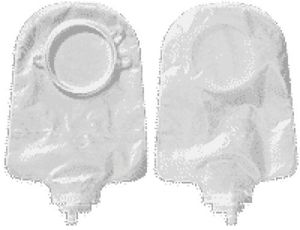

Odor Barrier.Rustle-free pouch.Color Transparent Drain Type Drainable Flange Size 2-3/4 Inch Flange Length 9 Inch Length Material Vinyl Panel No Panel Sterility NonSterile

Hollister CenterPointLock Two-Piece Urostomy Pouch 2-3/4" Flange (Box of 10 Each)

Odor Barrier.Rustle-free pouch.Color Transparent Drain Type Drainable Flange Size 2-3/4 Inch Flange Length 9 Inch Length Material Vinyl Panel No Panel Sterility NonSterile